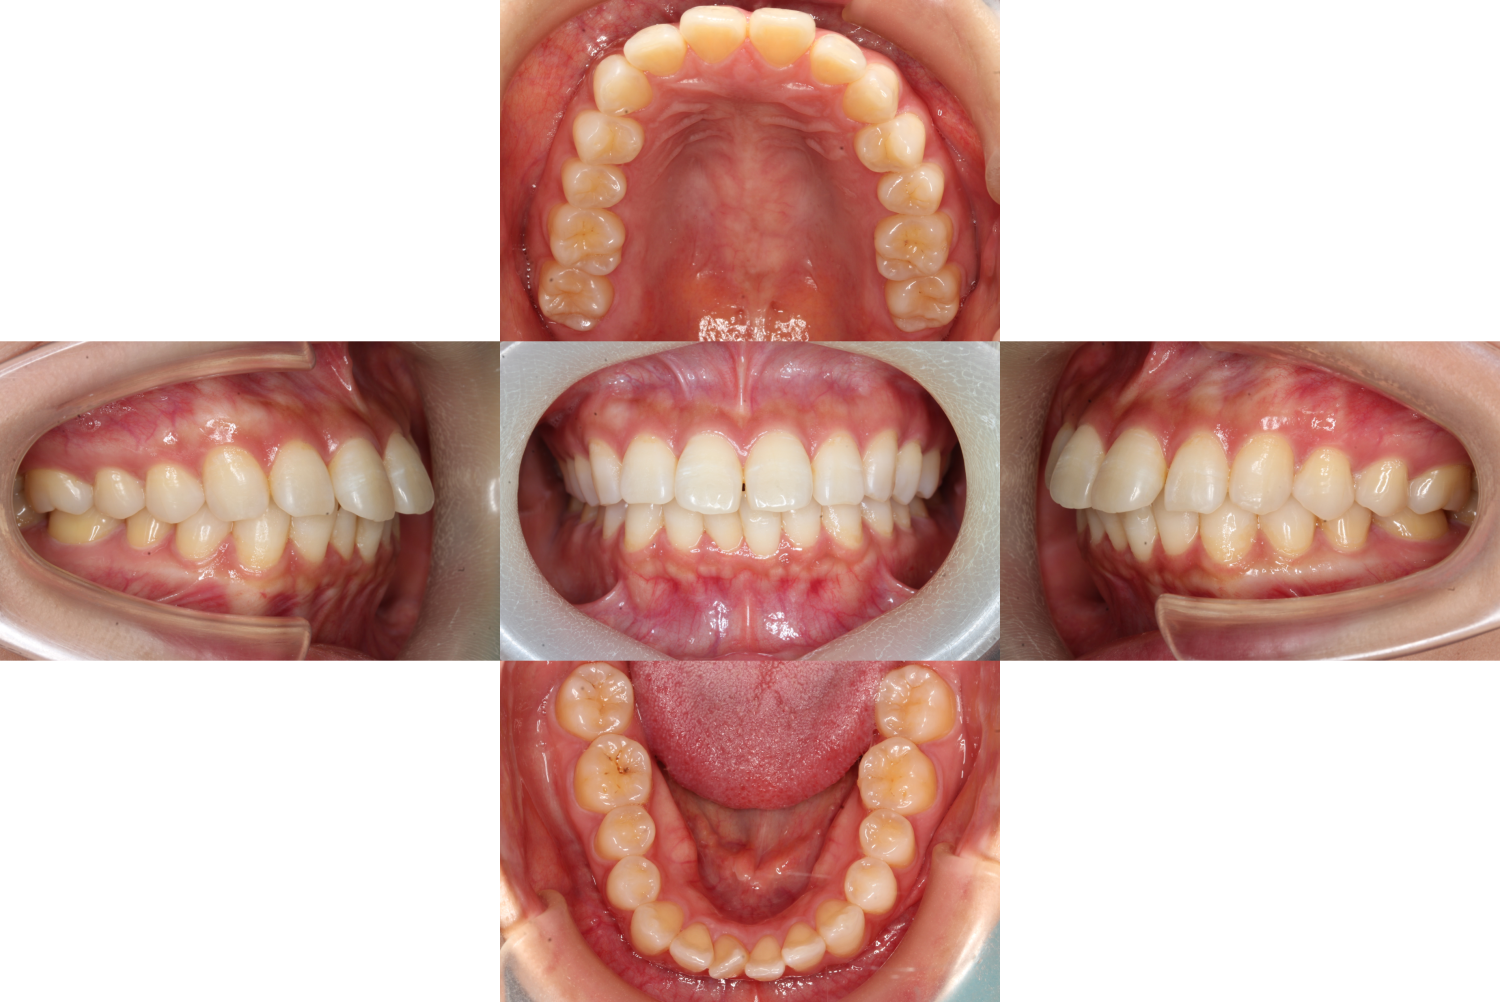

初診時の口腔内です。

患者様のお悩みは【口元を下げたい】

上の前歯だけが前に出ているように見えますが、

実際は上下とも前に出ているので上下合計4本抜歯をして

口元を下げていくことになりました。